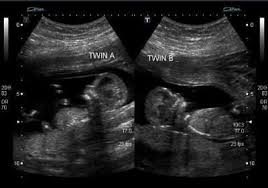

13 Week Twins In The Womb Week By Week, Twin Pregnancy Week By Week Symptoms And Development Pampers, That's because twin moms can have more of the pregnancy hormone hcg in their systems.. 2230 grams / 4lbs, 14oz. Your babies are approximately 7,5 cm (2.95 inches) from head to rump when you're 13 weeks pregnant with twins. If your nausea and vomiting is super severe, definitely bring it up to your ob. 3089 grams / 6lbs, 12oz. When do you start showing with twins?

Your babies are approximately 7,5 cm (2.95 inches) from head to rump when you're 13 weeks pregnant with twins. The average gestational age for twins at birth is 36 weeks. Estimated fetal weight for twins fetal growth chart fetal weight chart full term for twins twin fetal growth chart twin pregnancy week by week twin pregnancy: What would 13 weeks pregnant feel like? Jul 30, 2018 · 2561 grams / 5lbs, 10oz. When did you start showing with twins? When do you start showing with twins? Lowest prices from hundreds of sites all in one place.

Estimated fetal weight for twins fetal growth chart fetal weight chart full term for twins twin fetal growth chart twin pregnancy week by week twin pregnancy: It might soon be time to shop for a larger, more comfortable bra. We compiled some of the best tips, tricks, and facts about being 13 weeks pregnant with twins. Lowest prices from hundreds of sites all in one place. Your complete guide twin weight chart. Twin pregnancy symptoms and conditions. Your babies are approximately 7,5 cm (2.95 inches) from head to rump when you're 13 weeks pregnant with twins. Women who are carrying twins or multiples in their wombs tend to have it a tad more difficult than those who are pregnant with a single baby. Jul 30, 2018 · 2561 grams / 5lbs, 10oz. The first trimester is the first three months or until 13 weeks pregnant with twins. Lowest prices from hundreds of sites all in one place. If you're 13 weeks pregnant with twins, you might still be experiencing some morning sickness and fatigue. 3089 grams / 6lbs, 12oz.